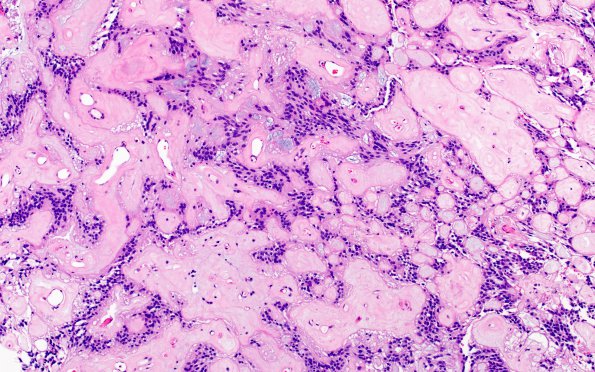

Washington University Experience | NEOPLASMS (GLIAL) | Ependymoma, myxopapillary | 11A3 Ependymoma, myxopapillary (Case 11) H&E 3

There is focal papillary architecture with cuboidal to elongated cells radially arranged along strongly hyalinized fibrovascular core. (H&E)